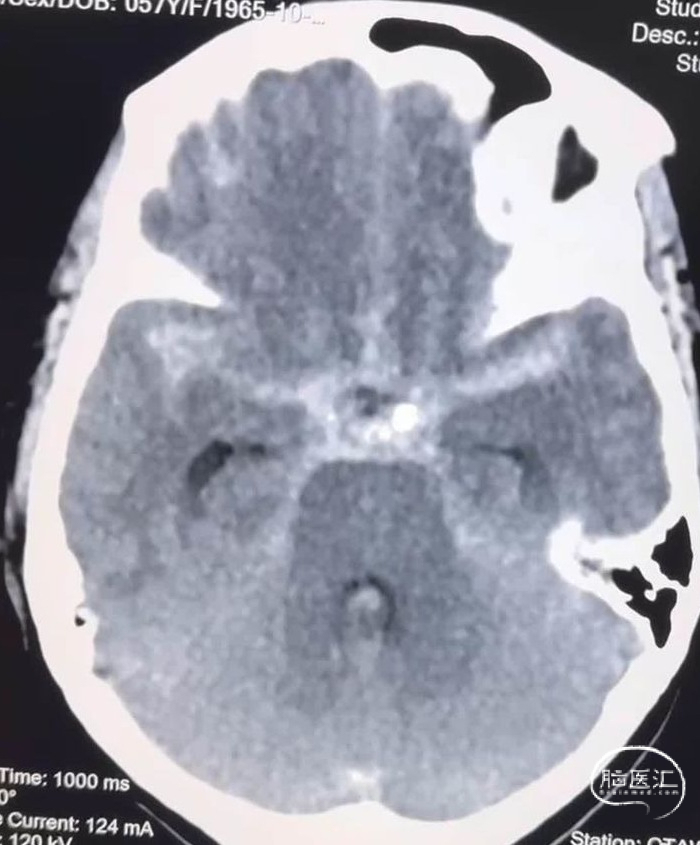

这是一个中年女性,广东佛山人,来青海旅游期间突然出现剧烈头痛、恶心、呕吐,由朋友送到距离最近的县医院,头颅CT示广泛性蛛网膜下腔出血,遂快速转入我院进入绿色通道进行快速评估。

快速行头颈部CTA显示罪魁祸首是左侧椎动脉颅内段夹层动脉瘤,动脉瘤呈三角形,基底很宽,进深很浅,根据经验,动脉瘤凸起部分只是冰山一角,往往凸起部分的对侧及远近端血管都会受到病变累及。